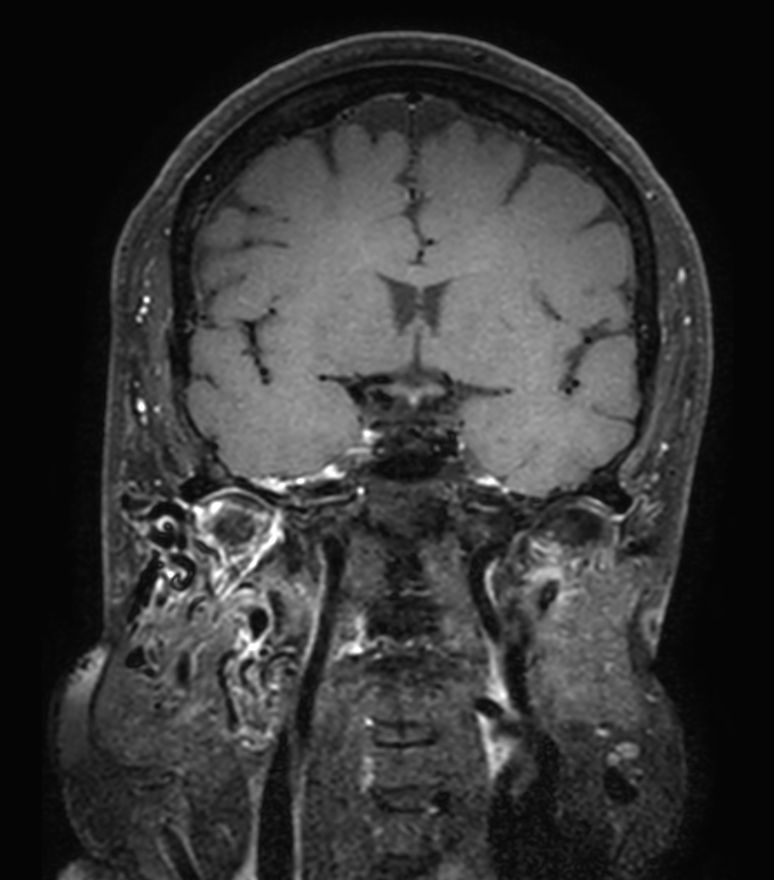

T1w TSE Compressed SENSE

T1w TSE mDIXON XD (+gado) Compressed SENSE